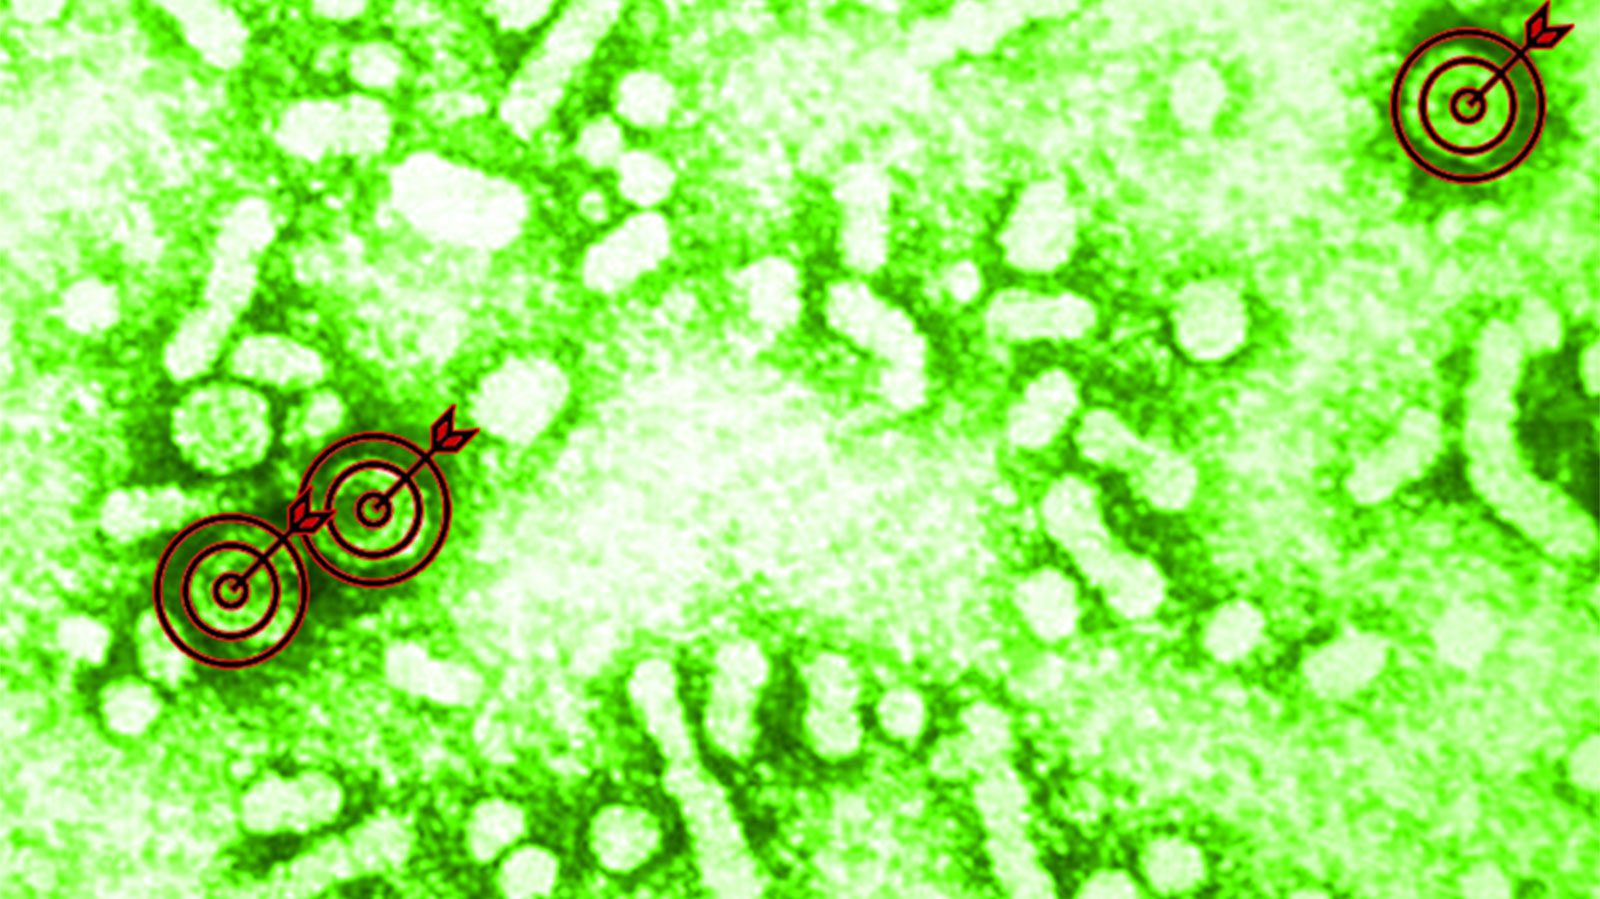

Virion Therapeutics, a pharmaceutical and medical research company based in the US, is currently trialling a medication called VRON-0200, which they hope will provide a functional cure for chronic HBV infection. VRON-0200 is able to mitigate hepatitis B’s exhaustion of the CD8+ T cells making these cells react at an earlier and faster level to the virus, as well as bringing other T cells into the fight against HBV infection. It also attacks parts of the HBV particles not normally targeted by the T cells.

In experimental results presented at the American Association for the Study of Liver Disease’s Liver Meeting 2025, Virion claimed that a single intramuscular dose of VRON-0200 induced HBV-specific immune activation and restoration, and HBsAg (the surface antigens of the hepatitis B virus, quantities of which are measured to see how much virus is in the body) reductions that were sustained and/or continued up to a year after the single dose, in the majority of chronically HBV-infected treated patients. The data, presented by Professor Grace Wong from the Chinese University of Hong Kong, also showed rapid and profound HBsAg declines when VRON-0200 was combined with antiviral medication.